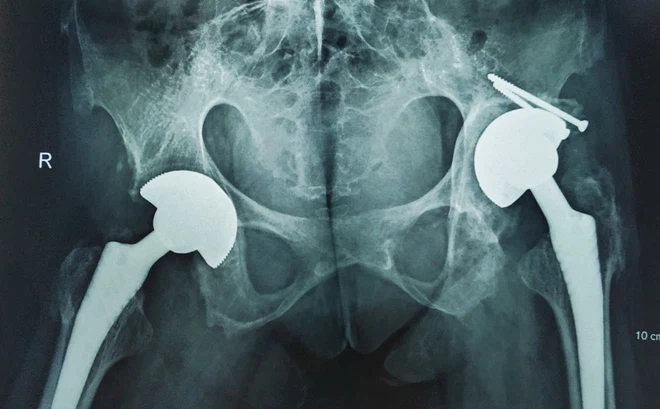

Chị H.T.T.H (45 tuổi) mắc bệnh viêm cột sống dính khớp từ nhỏ. Chị không thể cử động được khớp háng, không thể ngồi được mà lúc nào cũng phải nằm. Mọi sinh hoạt của chị phụ thuộc vào người thân chăm sóc.

Khi đến Bệnh viện Hữu nghị Việt Đức, chị H đã có biểu hiện biến chứng viêm dính khớp cột sống và viêm dính cứng khớp háng, chị không thể ngồi và bước đi được, mọi sinh hoạt rất khó khăn luôn phải có người hỗ trợ.

TS.BS Ngô Bá Toàn, Phó trưởng khoa Phẫu thuật Chấn thương chung, Bệnh viện Hữu nghị Việt Đức, cho biết: Ca mổ của bệnh nhân H là một ca mổ vô cùng phức tạp, cả hai khớp háng đã có biến chứng viêm dính biến dạng. Tình trạng viêm trong máu của bệnh nhân thường xuyên ở mức cao sẽ khiến cho vết thương lâu lành, thậm chí nhiễm trùng sau mổ.

Trước tình trạng của bệnh nhân, các bác sĩ đã hội chẩn đa chuyên khoa kỹ lưỡng và đưa đến quyết định mổ thay khớp háng 2 bên bằng kỹ thuật mổ ít xâm lấn.

Ngay sau mổ, chị H sức khỏe ổn định, hồi phục tốt và được hướng dẫn tập phục hồi chức năng sớm. Sau mổ 1 tháng, chị H đã có thể đi lại bình thường và được hướng dẫn tiếp tục tập luyện để có thể bình phục nhanh. Đây là niềm hạnh phúc to lớn mà chị H không dám mơ tới.

Các phương pháp điều trị chỉ có thể cải thiện triệu chứng và ngăn ngừa bệnh trở nên xấu đi. Phẫu thuật thay khớp háng được chỉ định trong trường hợp bệnh nhân đau kéo dài, hạn chế vận động và có phá hủy cấu trúc rõ trên hình ảnh X quang. Phẫu thuật chỉnh hình đối với cột sống được chỉ định khi cột sống biến dạng.